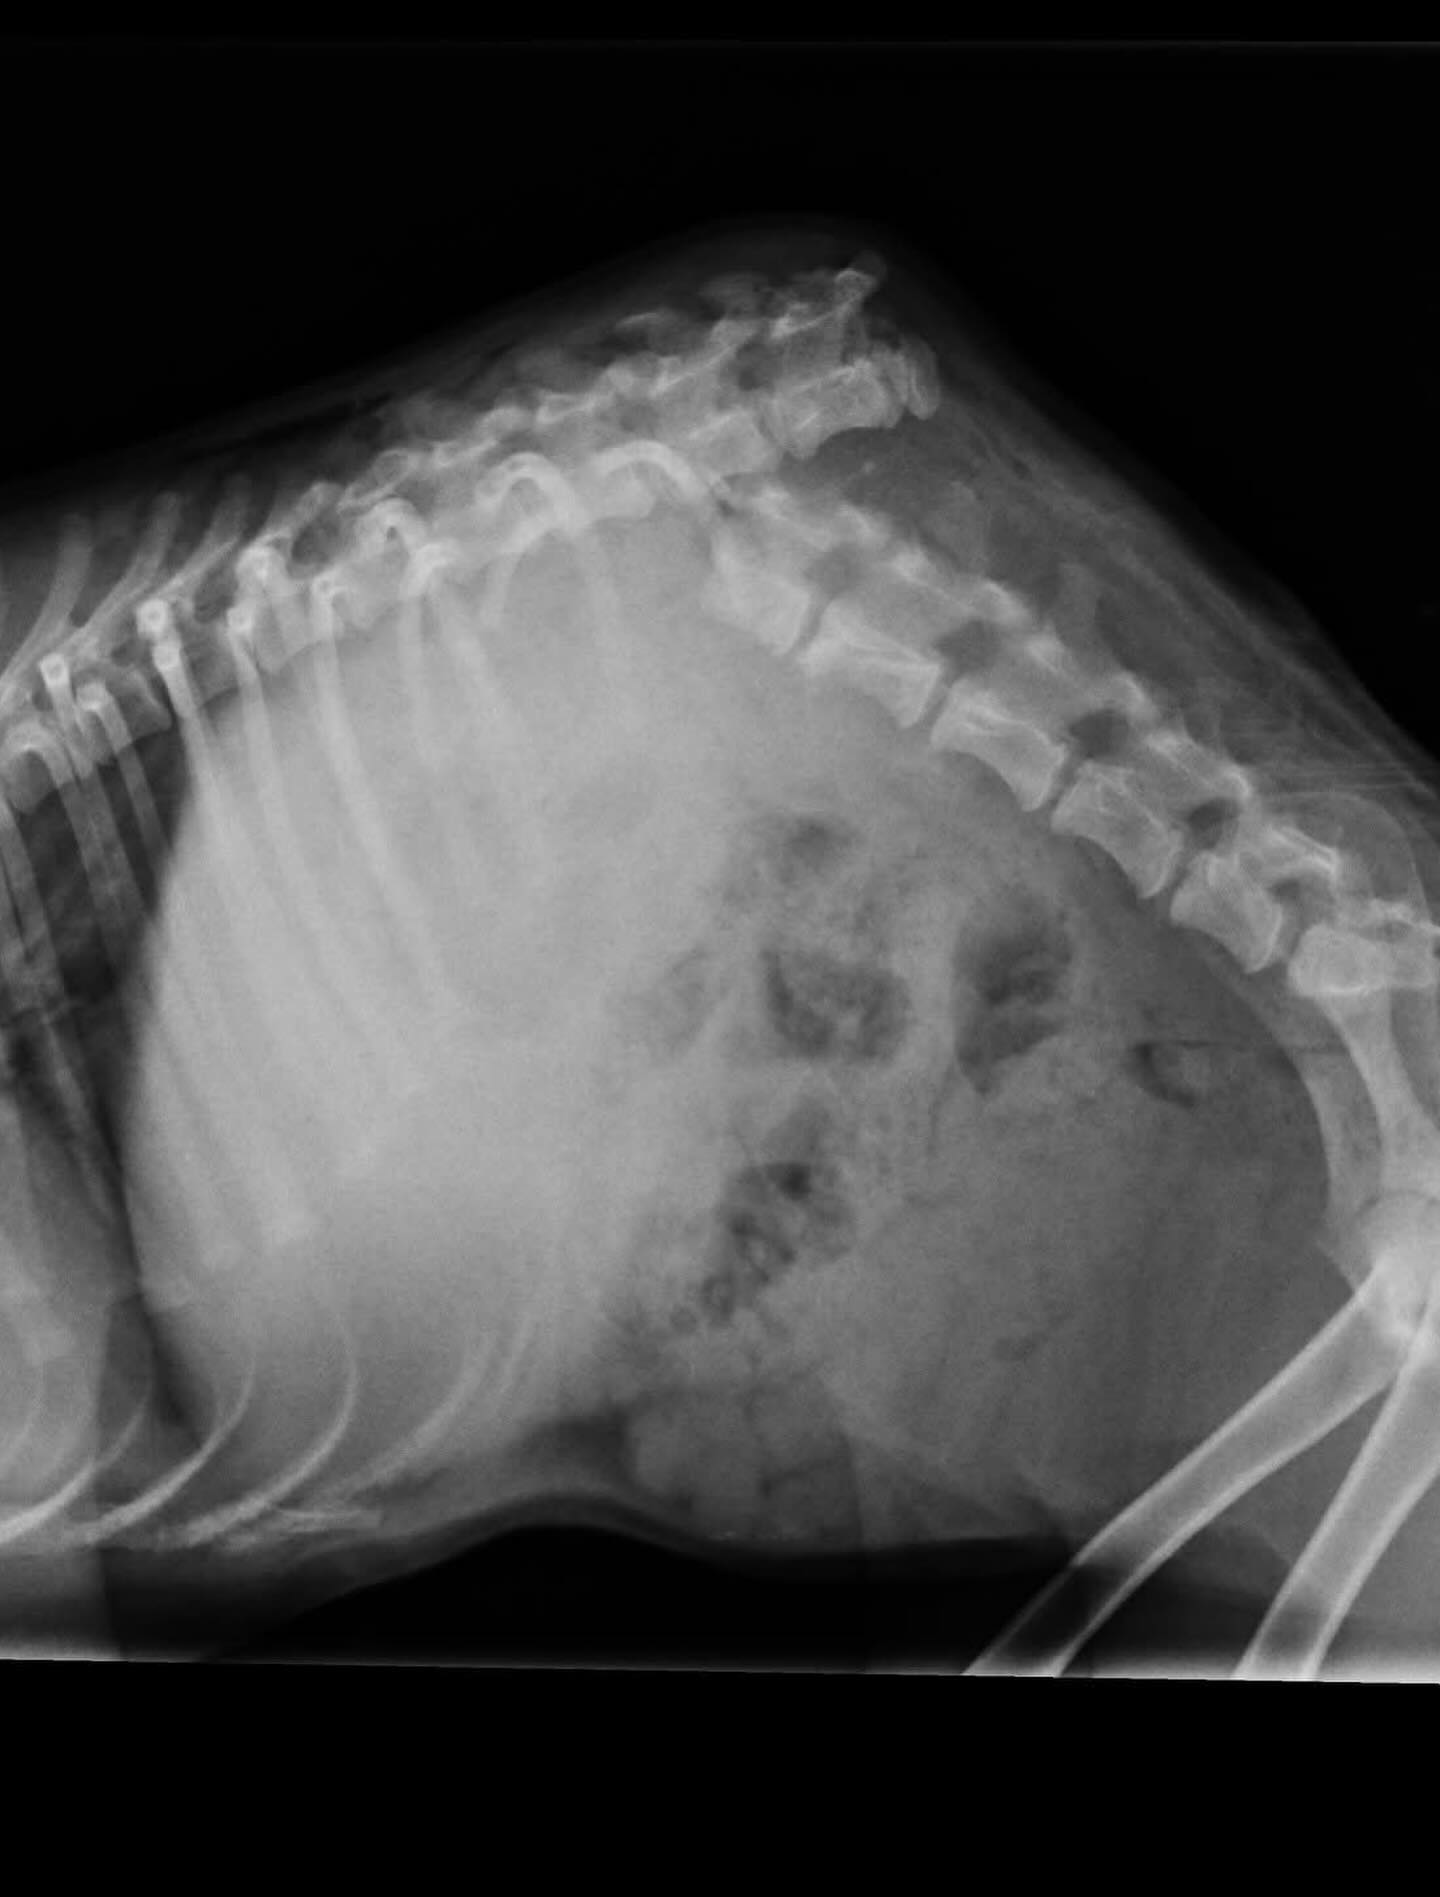

Tačiau tuo metu su kolega nusprendėme tiesiog pabandyti padaryti stebuklą. Atlikome vieną pirmųjų stuburo operacijų – nieko nežinodami, nemokėdami, bet labai tikėdami.

Viskas klostėsi sunkiai: lūžo varžtai, prasidėjo infekcija…

Tačiau mes nepasidavėme. Kovojome toliau. Stengėmės.

Viltė, kuri jau buvo ant mirties slenksčio, šiandien gyvena nuostabų gyvenimą ir juo džiaugiasi.